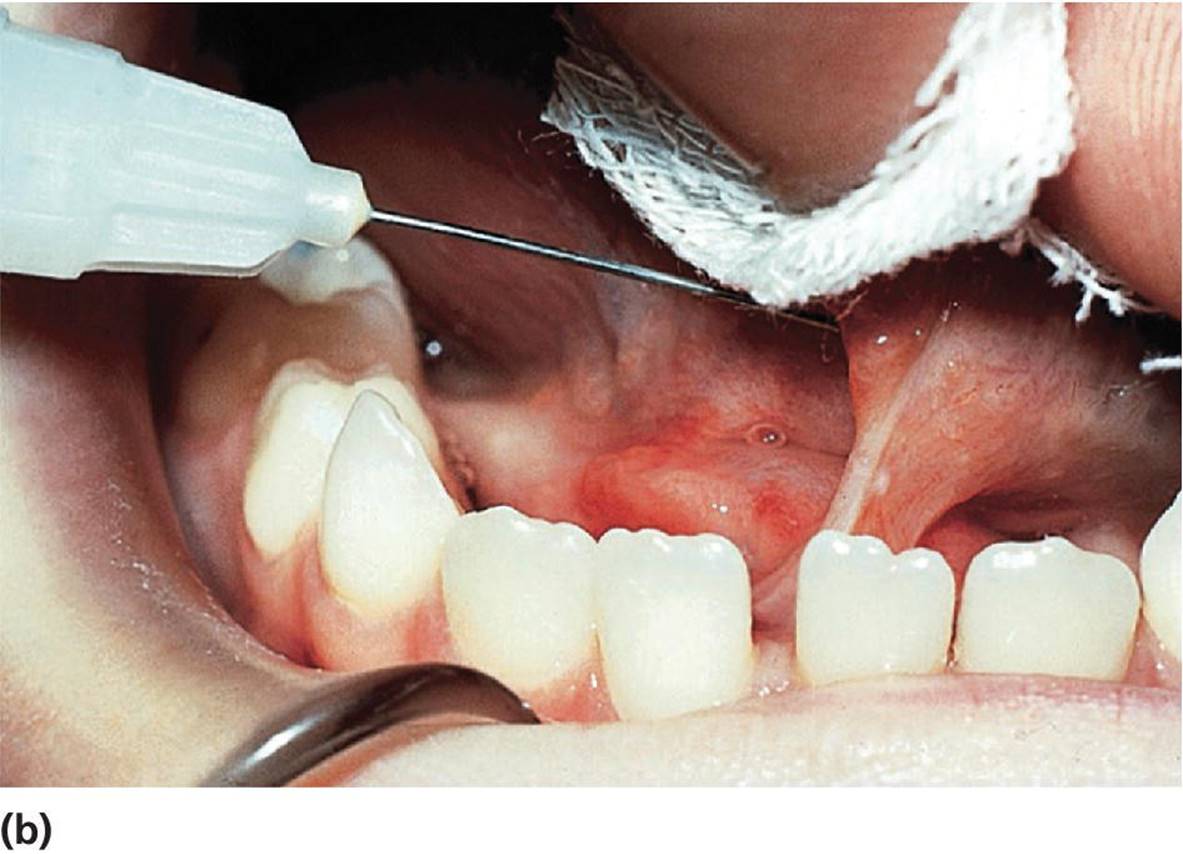

If a lingual frenulum is frequently traumatized by the mandibular incisors, causes retraction of the lingual gingiva or the mandibular incisors, or interferes with nourishment, speech development, or hygiene procedures it should be cut. It is vital to avoid two structures in this region, being the submandibular duct and the sublingual vein. The dissecting cut is best made lingual to the caruncles, parallel to the undersurface of the tongue, taking care not to go too deep (Figure 15.31).

Figure 15.31 Lingual frenuloplasty. (a) Lingual frenulum restricting the movements of the tongue. (b) Local anesthesia. (c) Curved hemostat is placed close to the tongue. (d, e) Frenulum is cut. (f) Healing after 10 days.